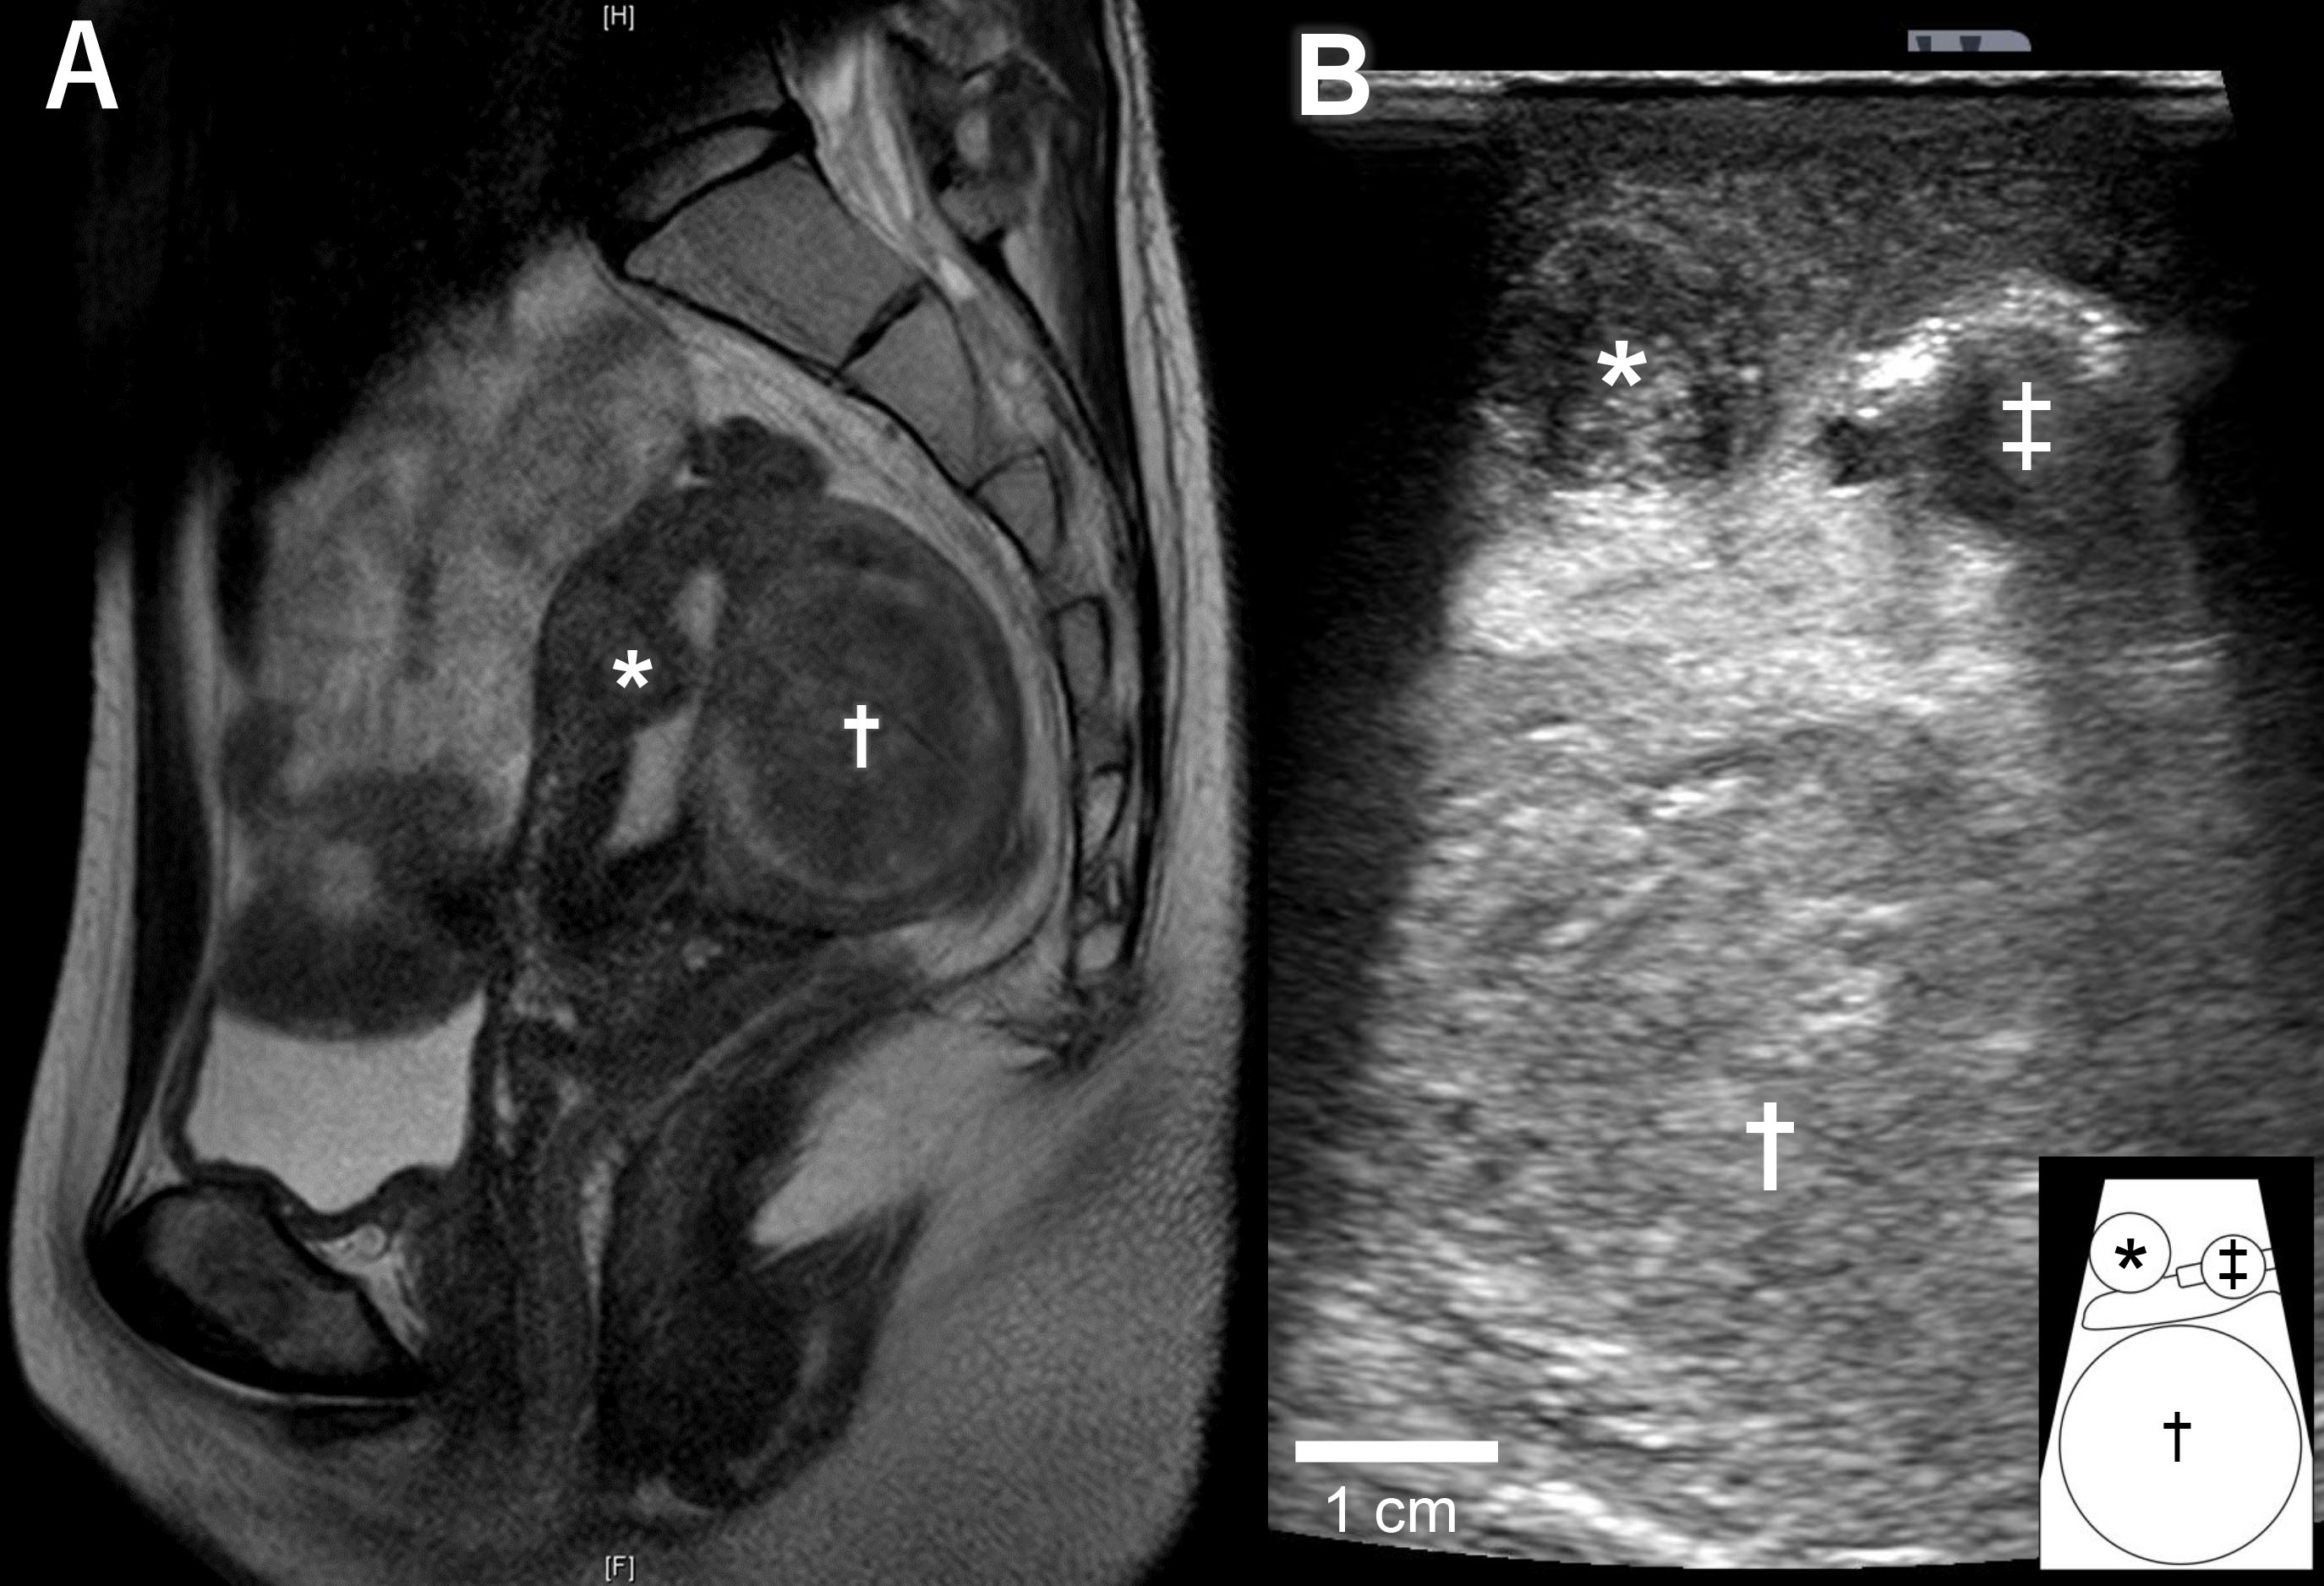

A 36-year-old nulligravida woman visited our clinic for an evaluation of her infertility. She was healthy, and her menses were regular and normal. Transvaginal ultrasonography revealed a type 2 submucosal myoma with a 60% myometrial extension measuring 15 mm in the anterior uterine wall and a type 4 intramural myoma (classified via guidelines from the International Federation of Gynecology and Obstetrics) measuring 49 mm in the posterior uterine wall. Magnetic resonance imaging suggested that the posterior myoma was a cellular leiomyoma (Fig. 1A). To make a definitive diagnosis regarding the intramural myoma, we planned a laparoscopic myomectomy. Furthermore, we planned to laparoscopically resect the submucosal myoma considering the myoma’s negative effect on implantation. Since the submucosal myoma was not visible from the external side of the uterus, we planned to use LUS to detect it. The location of the submucosal myoma was preoperatively assessed by transvaginal ultrasound sonography and magnetic resonance imaging. We measured the depth from the external side and the distance from the midline and fundus of the uterus. During the surgery, we used an ultrasound machine (Aplio a verifia CUS-AA000, Canon Medical Systems, Otawara, Tochigi, Japan) and a transducer (Linear array transducer PET-805LA, Canon Medical Systems, Otawara, Tochigi, Japan) with the detection frequency set at 7.0 MHz. We inserted the transducer through a 12-mm trocar (Fig. 1B). The submucosal myoma was visualized successfully with LUS immediately after the transducer was placed on the anticipated area of the anterior wall. Vasopressin (2 units diluted in 10 mL of saline) was injected precisely between the myoma and the myometrium under ultrasonography guidance (Fig. 2A,B). LUS also confirmed that the injected vasopressin effectively spread between the myoma and the myometrium (Fig. 2C). Using laparoscopic forceps and monopolar cautery, both the submucosal and the intramural myomas were successfully removed from the uterus without breaching the endometrium (Fig. 3A,B). The myomas were morcellated in a bag so that small fragments would not be scattered into the peritoneal cavity. The myoma beds were sutured to double to triple-layer closure with absorbable surgical thread. The postoperative course was uneventful, and the patient was discharged from the hospital as scheduled. No abnormal signs were detected at hospital visits 1 and 3 months after the surgery, and the initiation of fertility treatment was planned for 6 months after the surgery.

Fig. 1.Images of submucosal and intramural myomas. (A) Magnetic resonance image of the uterus. The submucosal myoma (*) in the anterior wall of the uterus was 40% intramural. The intramural myoma (†) in the posterior wall of the uterus was suggested as a cellular leiomyoma. (B) Image of laparoscopic ultrasonography during laparoscopic surgery. Transducer put on the anterior wall of the uterus, as shown in Fig. 2A, with a submucosal myoma (*) and an intramural myoma (†) clearly shown. A uterine manipulator is indicated by ‡. The schematic diagram at the bottom right explains the image of ultrasonography.